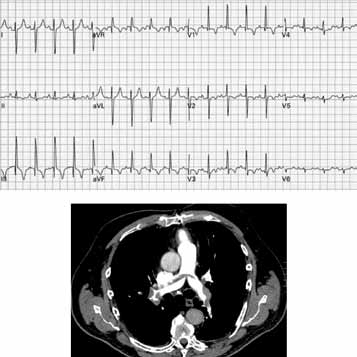

Paciente do sexo masculino, 67 anos de idade, com antecedentes de hipertensão arterial sistêmica, dislipidemia e neoplasia de próstata, submetido a tratamento cirúrgico com prostatectomia radical há 4 anos. Há cerca de 2 dias, relatou início de dor torácica ventilatório-dependente, tosse seca e dispneia limitante em repouso, associada a sudorese e mal-estar. Refere intensificação dos sintomas nas últimas horas, motivando sua procura pelo atendimento médico. O exame físico da admissão mostra o paciente em regular estado geral, taquidispneico em ar ambiente, queixando-se de dor em região retroesternal e base de ambos os pulmões, sudoreico e com extremidades frias, com SO2 = 84%, FR = 36 ipm, PA 80x40 mmHg, FC = 108 bpm. Ausculta cardíaca evidencia apenas ritmo regular taquicárdico. Ausculta pulmonar sem ruídos adventícios. Os exames laboratoriais evidenciaram: Hb = 10,9 g/dL, Ht = 29%, leucócitos = 8 200, plaquetas = 190 mil, ureia = 32 mg/dL, creatinina = 1,01 mg/dL, troponina I = 2,80 ng/dL (VN < 0,16), CKMB = 4,8 mg/dL (VN < 5,0), INR = 1,0, relação de tempos do TTPA = 1,10.

Foram solicitados eletrocardiograma de repouso e tomografia computadorizada de tórax, que se encontram ilustrados a seguir.

Em relação aos achados eletrocardiográficos do caso em questão, é correto afirmar que